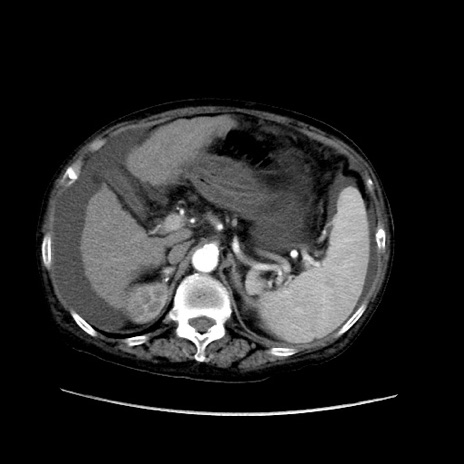

症例31(横断像)

【症例】80歳代 女性

【主訴】腹部膨満感

【現病歴】他院にて肝硬変にてフォロー中。1週間前から便秘、腹部膨満感、臍部腫瘤あり受診となる。

【既往歴】肝硬変

【身体所見】腹部膨隆あり、皮膚変化なし、疼痛なし。

【データ】WBC 4600、CRP 0.25